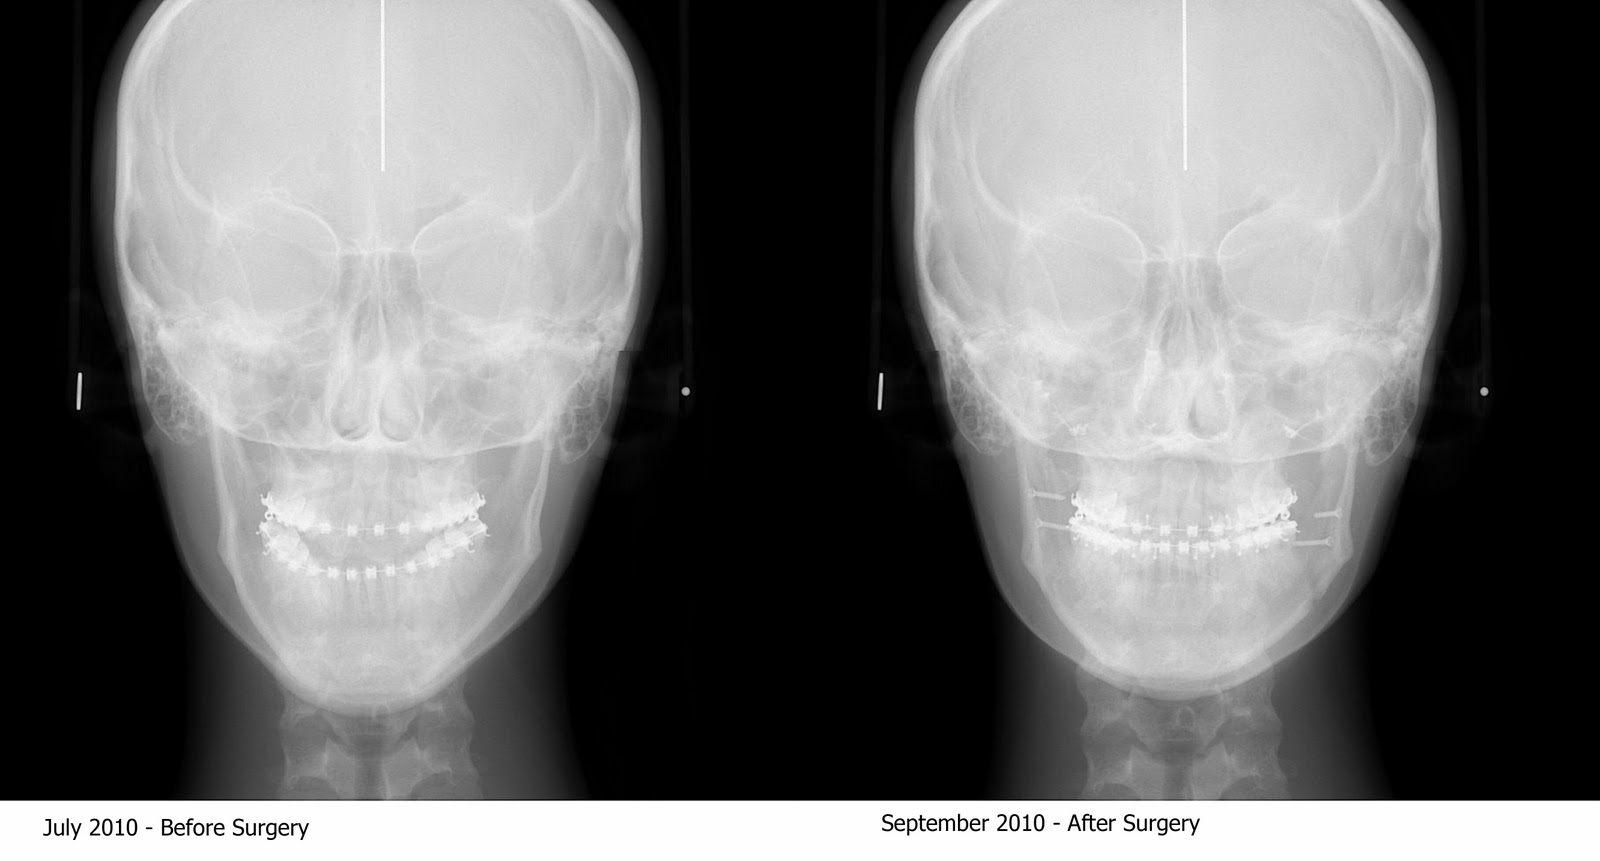

You can see the shape of my face changed pretty dramatically and that there's about a million screws holding it all together. I feel like I have a bionic jaw.